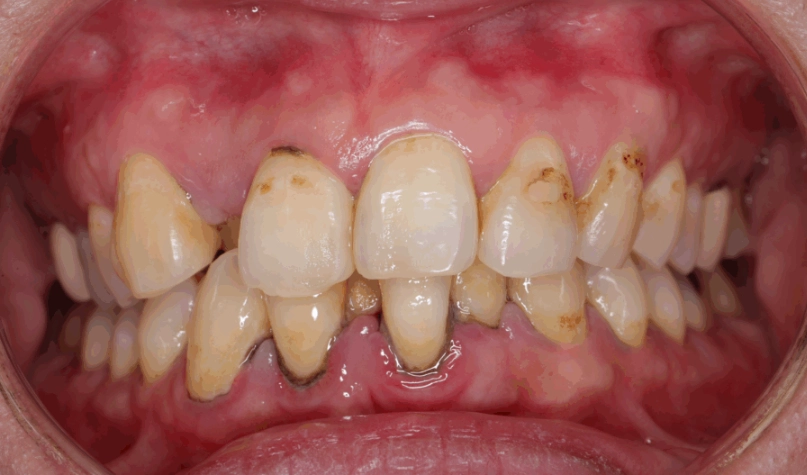

最麻煩的一點是,如果沒有及時清除,牙菌斑裡的細菌會分解食物中的糖分,產生酸性物質。這些酸會腐蝕牙齒琺瑯質,蛀牙就來了。同時,牙菌斑如果堆積在牙齦邊緣,會刺激牙齦發炎,紅腫流血,這就是牙齦炎。再放任下去,發炎往牙根深處走,破壞牙周組織,變成牙周病,牙齒就可能開始搖動。

這是你的終極防線。無論居家清潔多認真,總有一些死角會形成牙結石(鈣化的牙菌斑)。牙結石表面粗糙,會吸附更多牙菌斑,惡性循環。只有牙醫師能用超音波洗牙機將其震除。

根據台灣牙醫師公會全聯會的衛教資訊,建議每半年洗牙一次,並進行全面口腔檢查,及早發現蛀牙或牙周問題。這筆投資絕對比後續治療蛀牙或牙周病划算得多。

| 牙周深層清潔(牙根整平術) | 牙周囊袋內的牙菌斑與結石 | 牙醫師評估後進行 | 治療已形成的牙周病 |